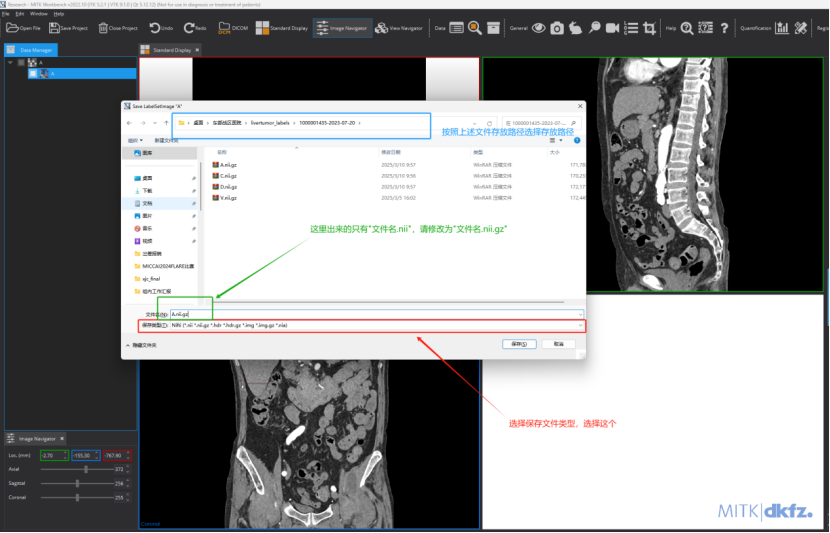

这里,按照不同的标注要求来命名(要求突出标注目标),比如此次标注的目标是肝肿瘤,可将每个病例的标注文件夹的父文件夹命名为livertumor_labels:

在livertumor_labels文件夹下面,包含各个病例标注对应的文件夹。以livertumor_labels这个文件夹为例,打开后的内容应该是:

于每个标注病例,里面的内容包括四个期的肿瘤标注文件,每个文件的命名必须和原始图像的命名保持一致。比如原始图像/images/1000001435-2023-07-20文件夹下A.nii.gz文件对应的标注路径应该在/livertumor_labels/1000001435-2023-07-20/A.nii.gz

标注完成后,需要对标注文件进行保存:鼠标右键点击此处,选择Save选项